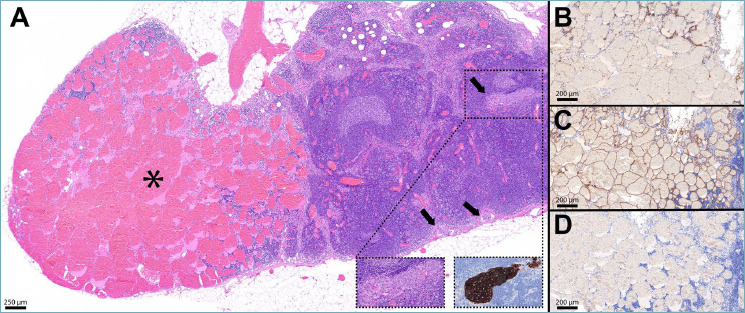

Secondary neoplastic lesions in lymph nodes are predominantly metastases from solid tumors, whereas primary lymph node hemangiomas are exceptionally uncommon, with only 24 well-documented cases in the literature. Histologically, they are characterized by endothelial cells that may appear flattened or enlarged, with variable vascular density, and the presence of stromal elements. Notably, the concurrent presence of a primary hemangioma and a metastasis from breast cancer - the latter being the most prevalent secondary lesion in axillary lymph nodes - represents an unprecedented observation. The unique case presented herein underscores the exceptional rarity of primary lymph node hemangiomas and demonstrates for the first time their possible coexistence with breast cancer metastasis within the same axillary lymph node. In sharing and discussing this case study, we pay homage to Professor Juan Rosai, whose work in redefining rare and complex diagnoses continues to enlighten our understanding of lymph node vascular lesions.